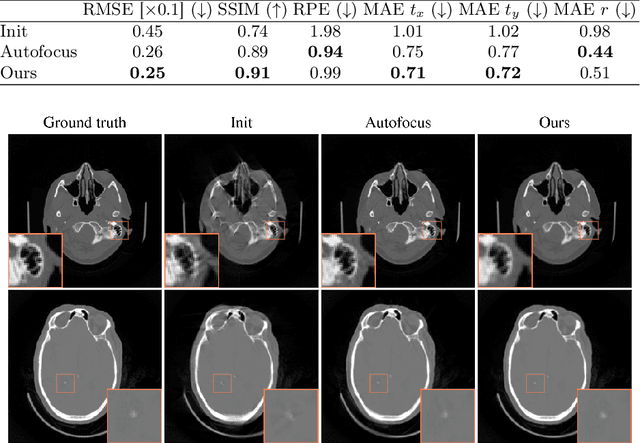

Abstract:Motion artifacts can compromise the diagnostic value of computed tomography (CT) images. Motion correction approaches require a per-scan estimation of patient-specific motion patterns. In this work, we train a score-based model to act as a probability density estimator for clean head CT images. Given the trained model, we quantify the deviation of a given motion-affected CT image from the ideal distribution through likelihood computation. We demonstrate that the likelihood can be utilized as a surrogate metric for motion artifact severity in the CT image facilitating the application of an iterative, gradient-based motion compensation algorithm. By optimizing the underlying motion parameters to maximize likelihood, our method effectively reduces motion artifacts, bringing the image closer to the distribution of motion-free scans. Our approach achieves comparable performance to state-of-the-art methods while eliminating the need for a representative data set of motion-affected samples. This is particularly advantageous in real-world applications, where patient motion patterns may exhibit unforeseen variability, ensuring robustness without implicit assumptions about recoverable motion types.